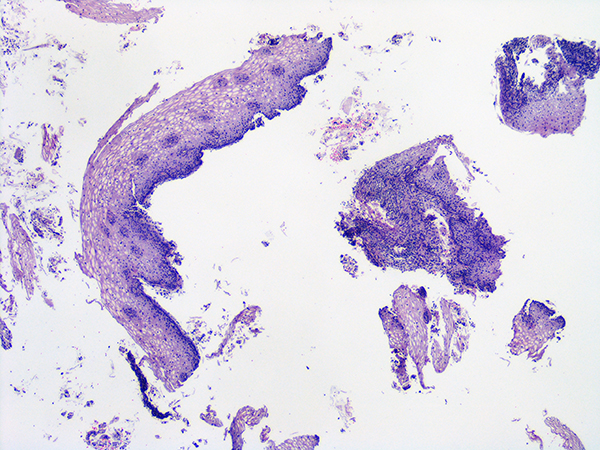

![]() HGSIL Soft Bx

Low Power |